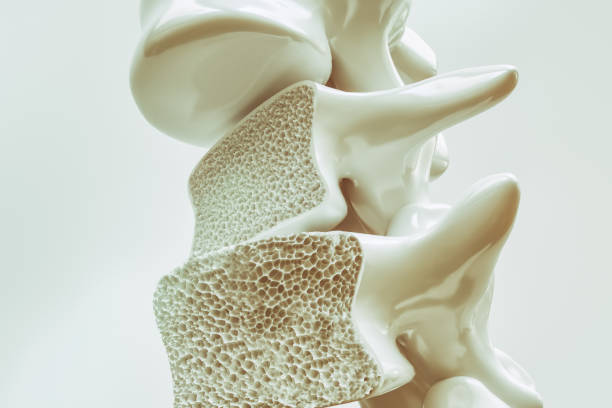

골다공증은 뼈 속에 있는 뼈가 점차적으로 없어지는 질병입니다. 이는 뼈가 흡수되어 뼈의 밀도가 감소하게 되어 발생합니다. 뼈의 밀도가 감소하면 뼈가 약해지고, 따라서 골절이 쉽게 발생할 수 있습니다. 골다공증은 주로 고령자에게서 발생하지만, 젊은 세대에서도 발병할 수 있습니다.

골다공증을 치료하려면 약물 치료가 필요할 수 있습니다. 이 약물은 뼈의 손상을 예방하고 뼈 밀도를 높일 수 있습니다. 골다공증 약물은 개별 환자의 상태에 따라 적절하게 선택되어야 하며, 의사의 지시에 따라 복용해야 합니다.